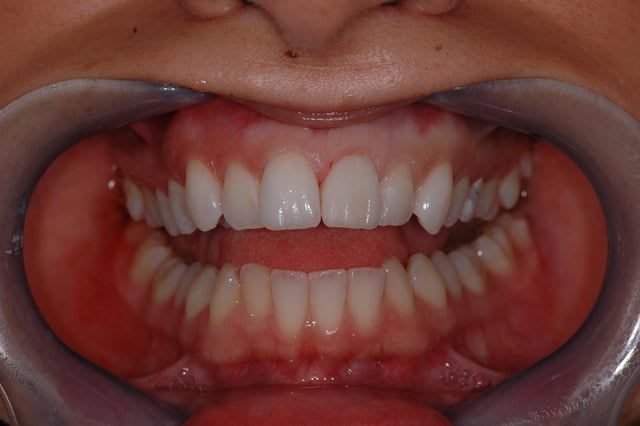

j'ai pas fait les bras à cette petite, mais je lui ai fait sa facette.

donc voici en presque en direct live le cas terminé...

facette feldspatique. vu l'épaisseur on a droit à une seule cuisson, donc faut pas se rater sur la teinte ou la forme.

teinte = OM2 teintier vita 3D master ! c'est dire si elle a les dents blanches la demoiselle. au départ de cas, je pensais qu'on était sur un A2, mais voila ce que donne la provisoire qui contrairement aux apparences était bien en A2.